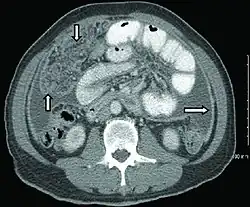

Extrapulmonary tuberculosis

CT scan of peritoneal tuberculosis, a form of extrapulmonary tuberculosis. The omentum and peritoneal surfaces are thickened (arrows).[4]

Peritoneal tuberculosis may mimic peritoneal carcinomatosis on CT scan.[4]